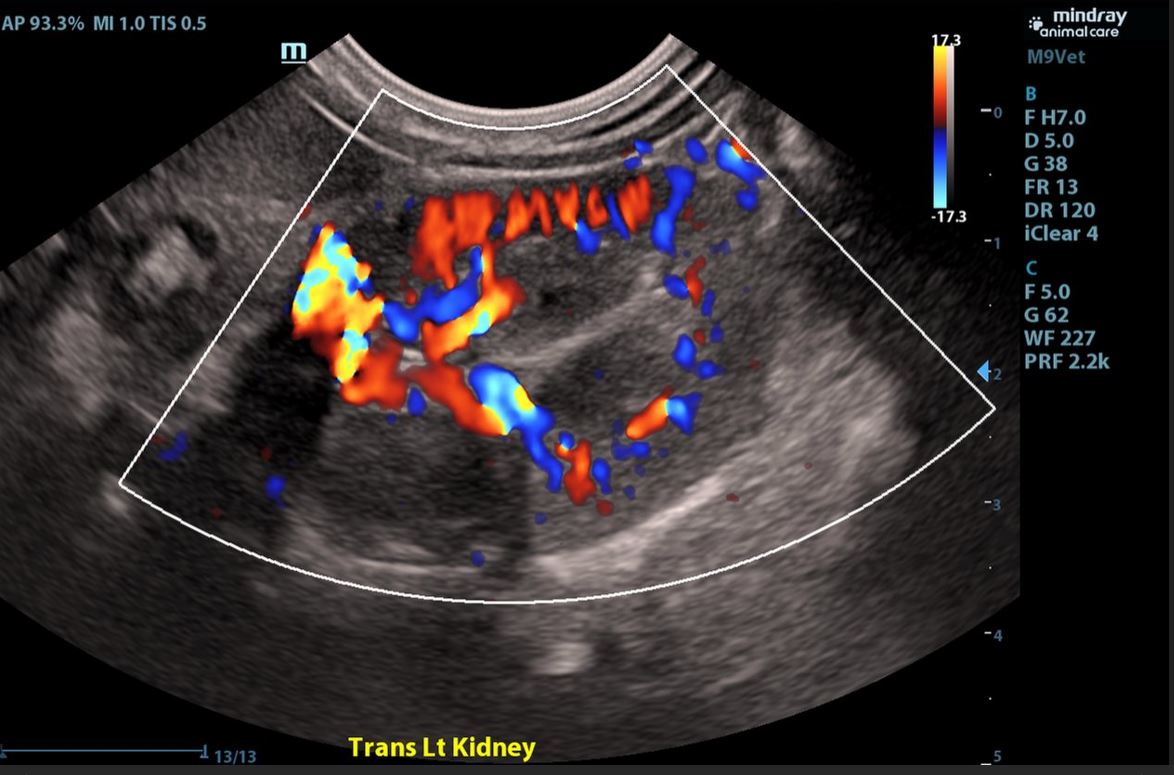

- Kidneys and Urinary Bladder